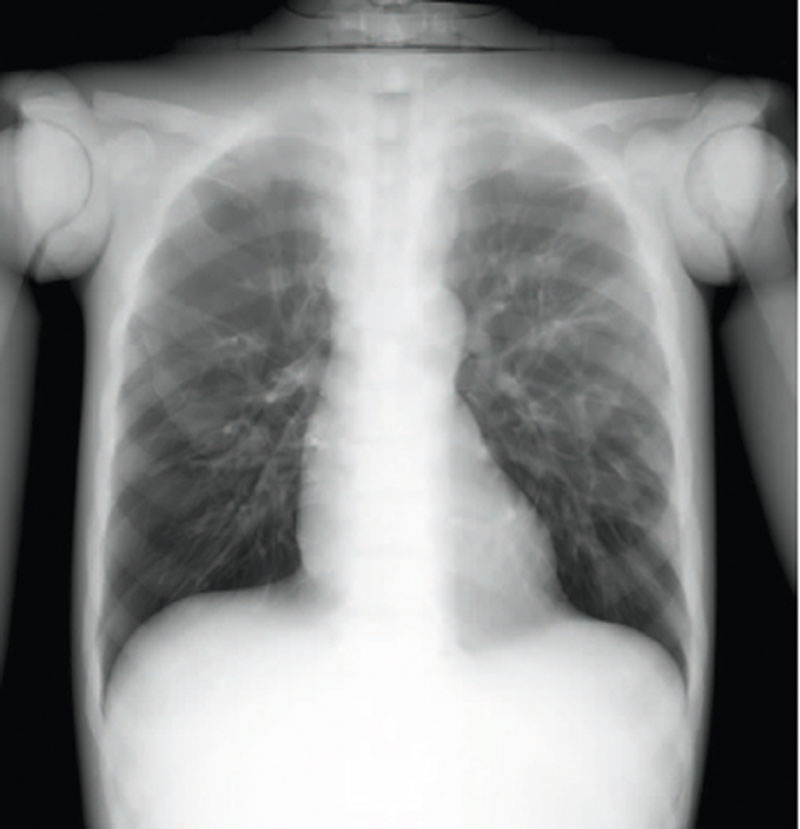

Ein einzigartiges Ganzkörperphantom für CT bietet eine Vielzahl von Ausbildungs- und Forschungsmöglichkeiten. Das Phantom kann auch für normales Röntgen benutzt werden und gibt lebensnahe Bilder. Es benden sich keine Metallteile oder Flüssigkeiten im Phantom. Die wichtigen Gelenke haben eine menschenähnliche Beweglichkeit und erlauben vielfältige Positionen für die Übung. Das Phantom kann in 10 Teile zerlegt werden. Die verbesserten Schultergelenke erlauben es, die Arme nach oben zu bewegen. Die künstlichen Organe sind anatomisch korrekt und haben entsprechende HU-Zahlen.

- Lungen mit Pulmonalgefäßen

Radiologische Absorption und Hounsfield-Nummer ähnlich dem menschlichen Körper.